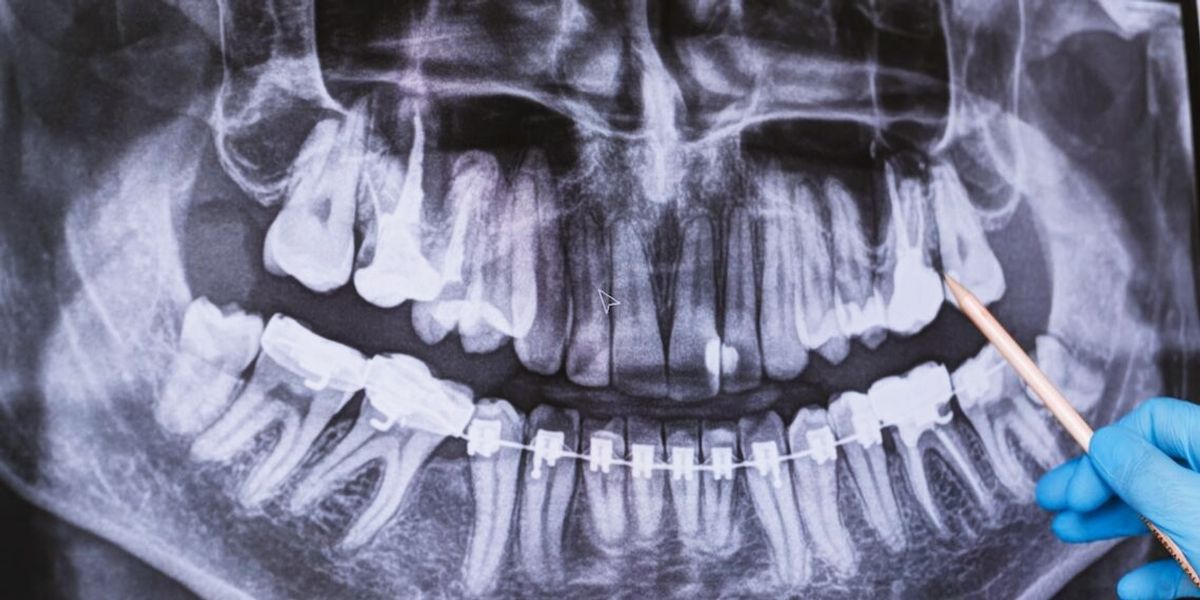

Desarrollan medicamento revolucionario que promete regenerar dientes caídos en adultos

Científicos japoneses ha desarrollado un fármaco que gracias a su revolucionaria fórmula, permitirá que nuestros dientes crezcan nuevamente, pese haberlos perdido en el pasado.

Los dientes forman una de las partes más sensibles del cuerpo humano, por lo que, sonreír teniendo problemas dentales se vuelve en un verdadero problema de autoestima para muchas personas. Afortunadamente, esto podría cambiar muy pronto, ya que un equipo de científicos japoneses ha desarrollado un fármaco que podría cambiar esta situación para siempre; gracias a su revolucionaria fórmula que permitirá que nuestros dientes crezcan nuevamente, pese haberlos perdido en el pasado.